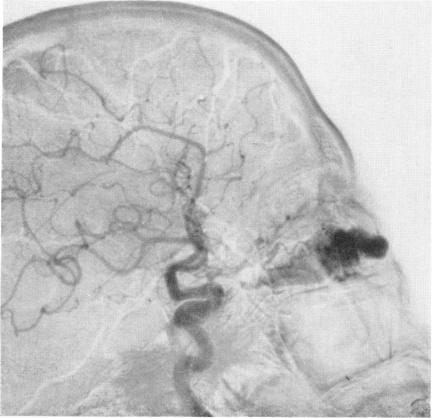

Arteriography and phlebography in the diagnosis of orbital affections.

Bull N Y Acad Med. 1968 Apr;44(4):409-30.